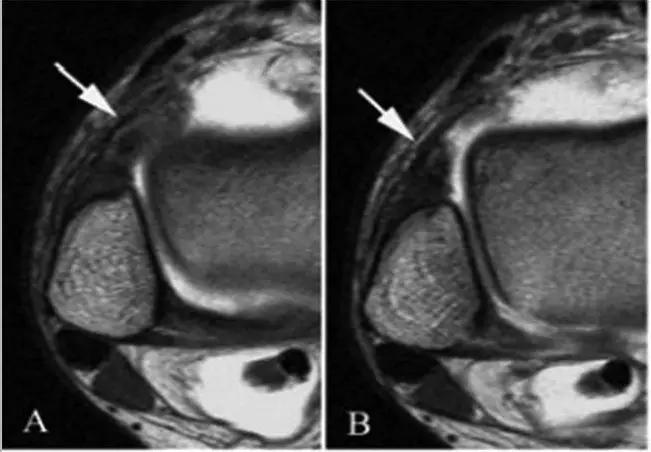

- 影像学表现为外侧沟内异常软组织或(和)前胫腓韧带(AITFL)异常肥厚。

①踝关节外侧沟内异常软组织

②前胫腓韧带(AITFL)异常肥厚

T1WI FS C+

异常增厚的前胫腓韧带